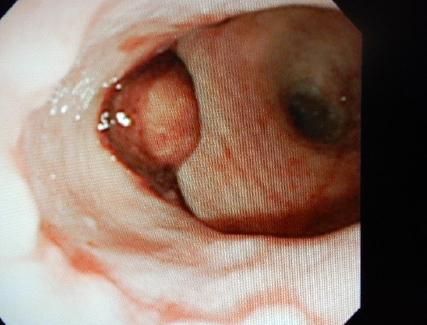

ケース:11歳10ヶ月、去勢済みの男の子、ネコちゃん

昨夜から排尿がなく、嘔吐があるとのことで来院されました。一般身体検査では、膀胱内に貯尿はなく、血液検査では腎臓の数値が著しく上昇していました。急性腎不全を疑い、入院治療となりました。まず、尿道内カテーテルを挿入し輸液療法と利尿剤投与を行いましたが、排尿は見られず、腎臓の数値も悪化していきました。おしっこが出ないので、体はむくみ、尿毒症による口内炎のため、よだれが出ている状態でした。ご家族とご相談の上、麻酔のリスクはありますが、腹腔内チューブを設置し、腹膜透析を行うことにしました。また、麻酔中に食道チューブの設置も行いました。腹膜透析は腹腔内チューブを介してお腹の中に透析液を注入し、2時間毎に回収しては新しい透析液を注入します。開始2日目に少量の排尿が見られるようになり、その後徐々に尿の生産が増えていき、腎臓の数値も低下していきました。透析開始6日目には腎臓の数値も低下し、排尿も見られるようになったため、腹腔チューブを抜去しました。その後も輸液療法を続けたところ、大量の排尿が見られたため、入院16日目に退院することが出来ました。退院後、しばらくは口内炎等で自力ではご飯が食べれないため、腎臓病用の流動食を食道チューブから入れていただいていましたが、退院3週間後には、口から元通り食べられるようになったため、食道チューブも抜去しました。